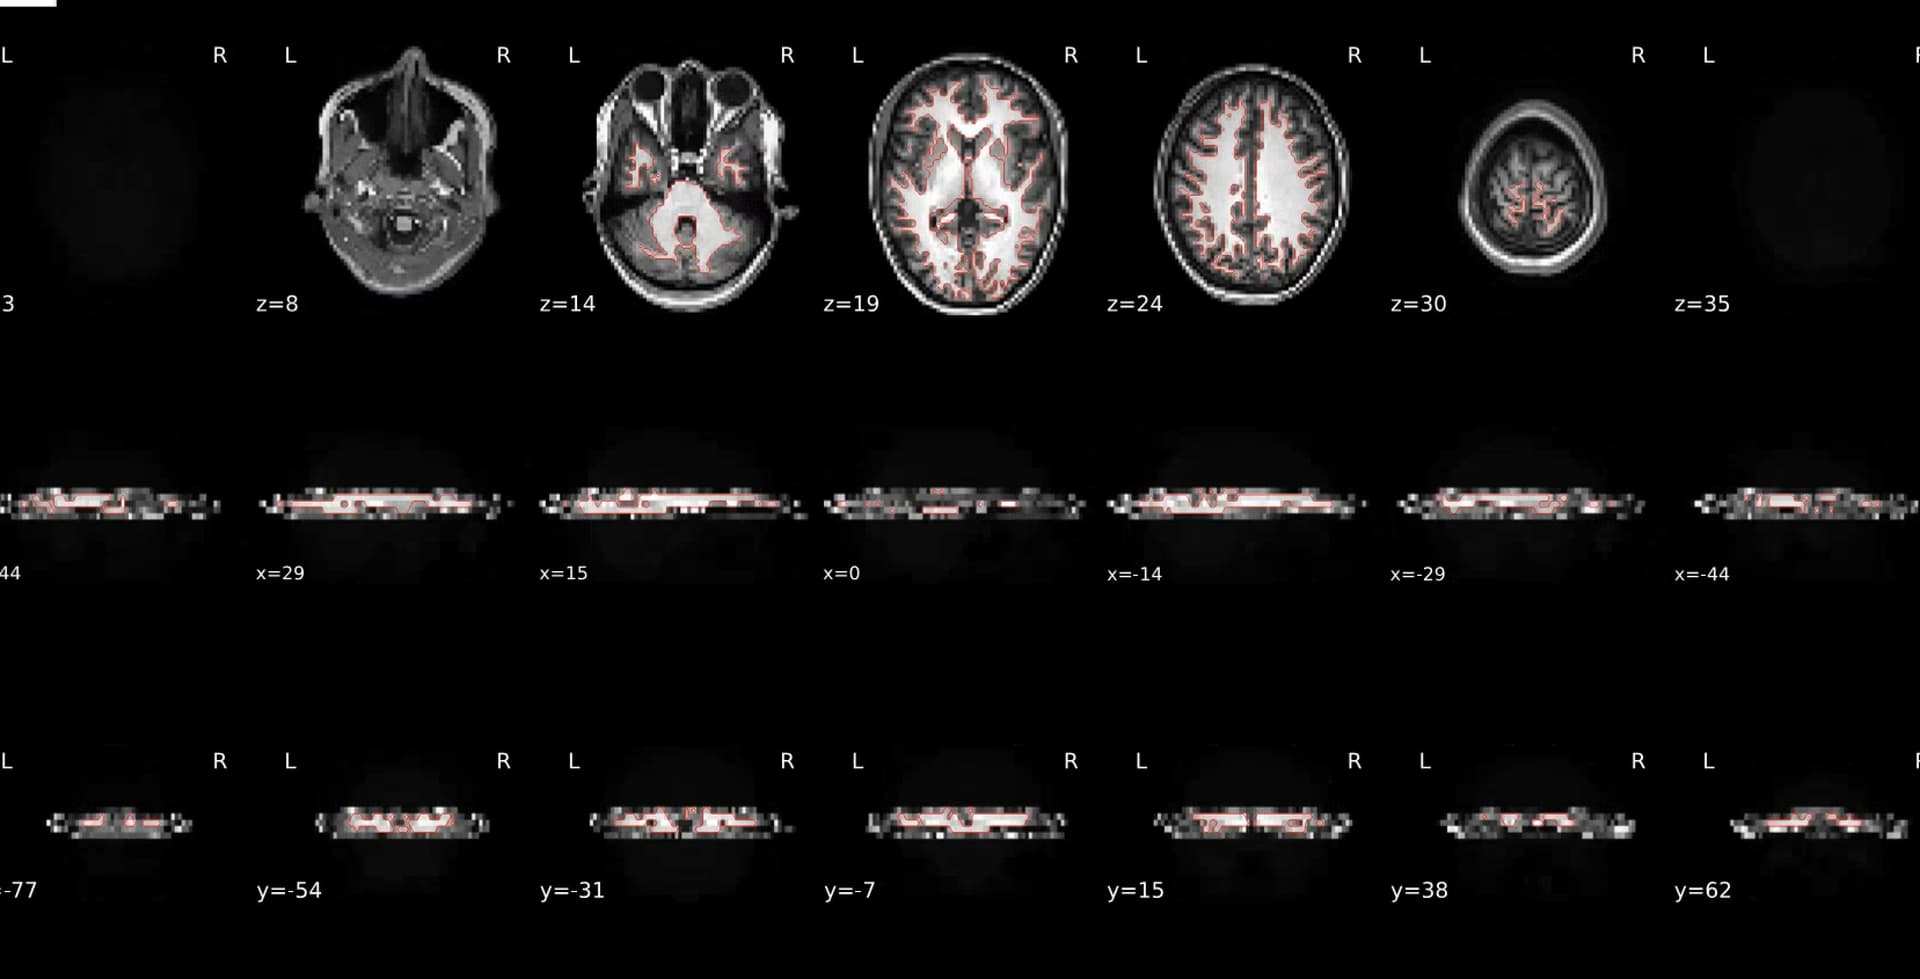

I am using ASLPrep version 25.1.0 after running fMRIPrep. With this I am reusing the freesurfer output produced from fmriprep where I forced bbr. When inspecting ASLPrep after upgrading to version 25.1.0 and re-running my data, coregistration is extremely poor. Looking at the reports, it is using mri_coreg

but all the examples I can find show it should be using FLIRT. My command is in the image below. Any help in this would be great as I have tried multiple different inputs to aslprep and I continue to get poor registration when 0.7.5 produced acceptable registration for the same data.